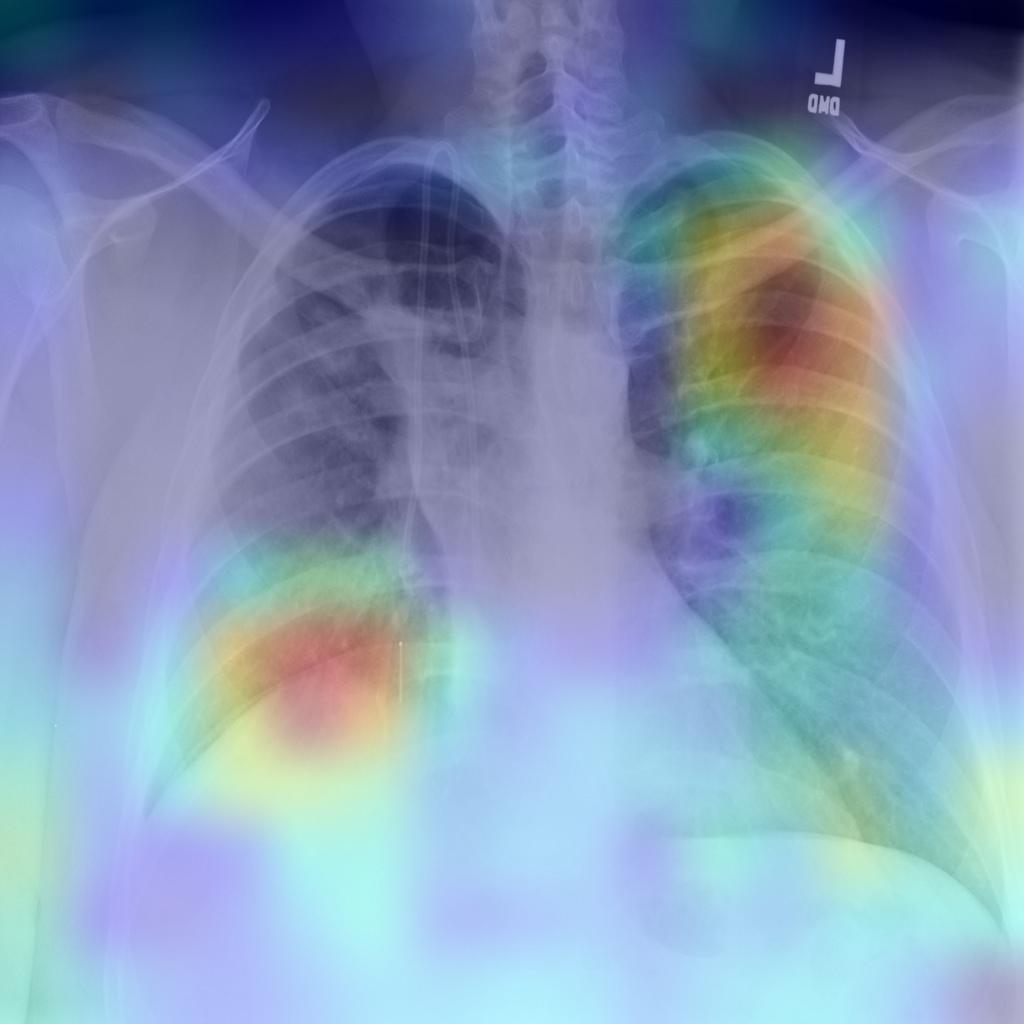

In our evaluation, we applied the Grad-CAM visual interpretation method to visually depict the salient areas where ECOVNet emphasizes the classification decision for a given chest X-ray image. Accurate and definitive salient region detection is crucial for the analysis of classification decisions as well as for assuring the trustworthiness of the results. In order to locate the salient area, the feature weights with various illuminations related to feature importance are used to create a two-dimensional heat map and superimpose it on a given input image. Figure 9 shows the visualization results of locating Grad-CAM using ECOVNet for each model snapshots. This salient area locates the area of each category area in the lung that has been identified when a given image is classified as COVID-19 or normal or pneumonia. As shown in Figure 9, for COVID-19, a ground-glass opacity(GGO) occurs along with some consolidation, thereby partially covering the markings of the lungs. Hence, it leads to lung inflammation in both the upper and lower zones of the lung. When examining the heat maps generated from the COVID-19 chest X-ray, it can be distinguished that the heat maps created from snapshot 2 and snapshot 3 points to the salient area (such as GGO). However, in the case of the normal chest X-ray, no lung inflammation is observed, so there is no significant area, thereby easily distinguishable from other classes, i.e., COVID-19 and pneumonia. As well, it can be observed from the chest X-ray for pneumonia is that there are GGOs in the middle and lower parts of the lungs. The heat maps generated for the pneumonia chest X-ray are localized in the salient regions with GGO, but for the 4th snapshot model, it appears to fail to identify the salient regions as the heat map highlights outside the lung. Accordingly, we believe that the proposed ECOVNet provides sufficient information about the inherent causes of the COVID-19 disease through an intuitive heat map, and this type of heat map can help AI-based systems interpret the classification results achieved from the proposed architecture.

Refer to captionRefer to captionRefer to captionRefer to captionRefer to captionRefer to captionRefer to captionRefer to captionRefer to captionRefer to captionRefer to captionRefer to captionRefer to captionRefer to captionRefer to captionRefer to captionRefer to captionRefer to captioni=1𝑖1i=1i=2𝑖2i=2i=3𝑖3i=3i=4𝑖4i=4i=5𝑖5i=5COVID-19Normal Pneumonia Grad-CAM Visualization for ith Snapshot Model

Figure 9: Grad-CAM visualization for the proposed ECOVNet considering the base model EfficientNet-B5. A total of 5 (five) model snapshots were generated during the training process.